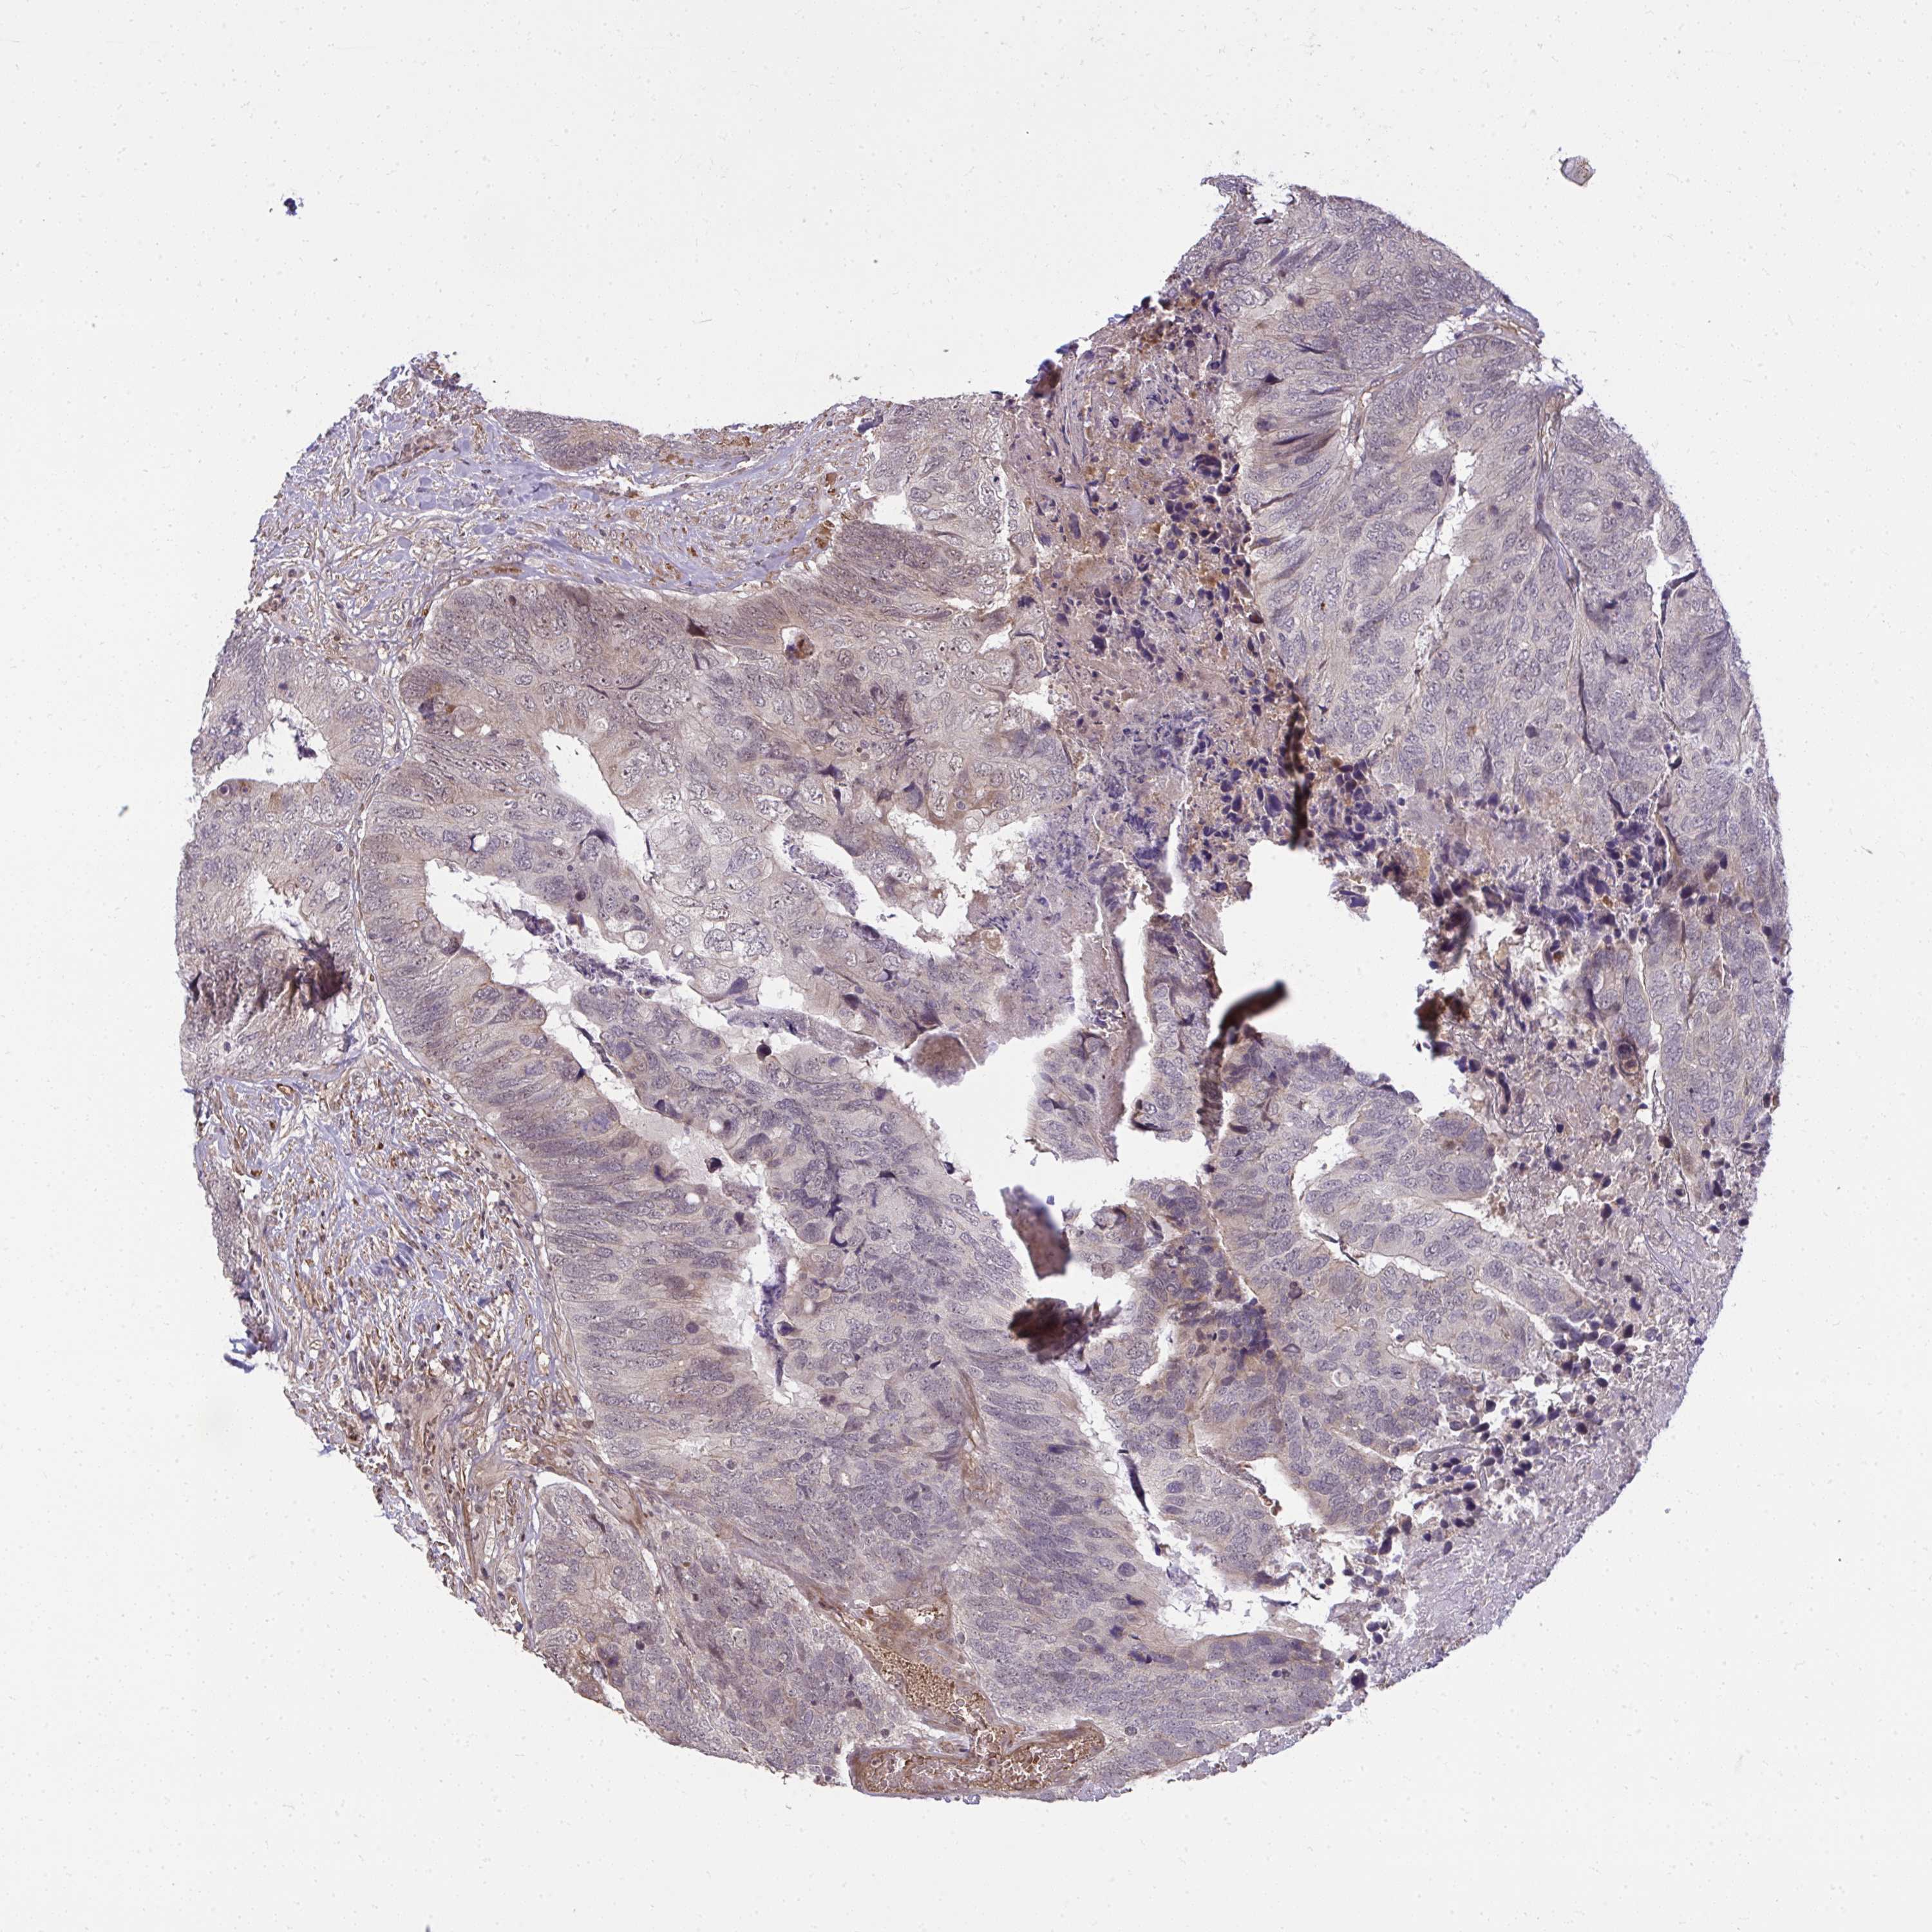

BRCA TCGA BRCA VALIDATION PROTEIN EXPRESSION

Breast cancer

Human cancer